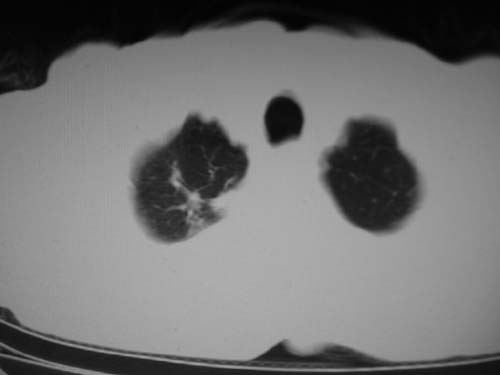

男,80岁

肺a高压征[左肺a狭窄?];肺,胸膜tb

右肺上叶结核;左肺门占位?建议增强扫描.

左下肺静脉扩张,原因?建议cta

左肺动脉异常增粗,建议增强。

1)考虑肺动脉狭窄。2)右肺上叶继发性肺结核。3)右侧胸膜增厚、钙化,左侧胸膜反应。

肺动脉瘤。建议先行ct增强扫描

左肺动脉异常增粗,考虑肺动脉狭窄可能。

右肺上叶继发性肺结核。

右侧胸膜增厚、钙化,左侧胸膜反应。

肺动脉段突出,左右肺门不等大,左肺门明显增大,肺动脉干及左肺动脉明显增宽,考虑先天性肺动脉狭窄瓣膜狭窄型。